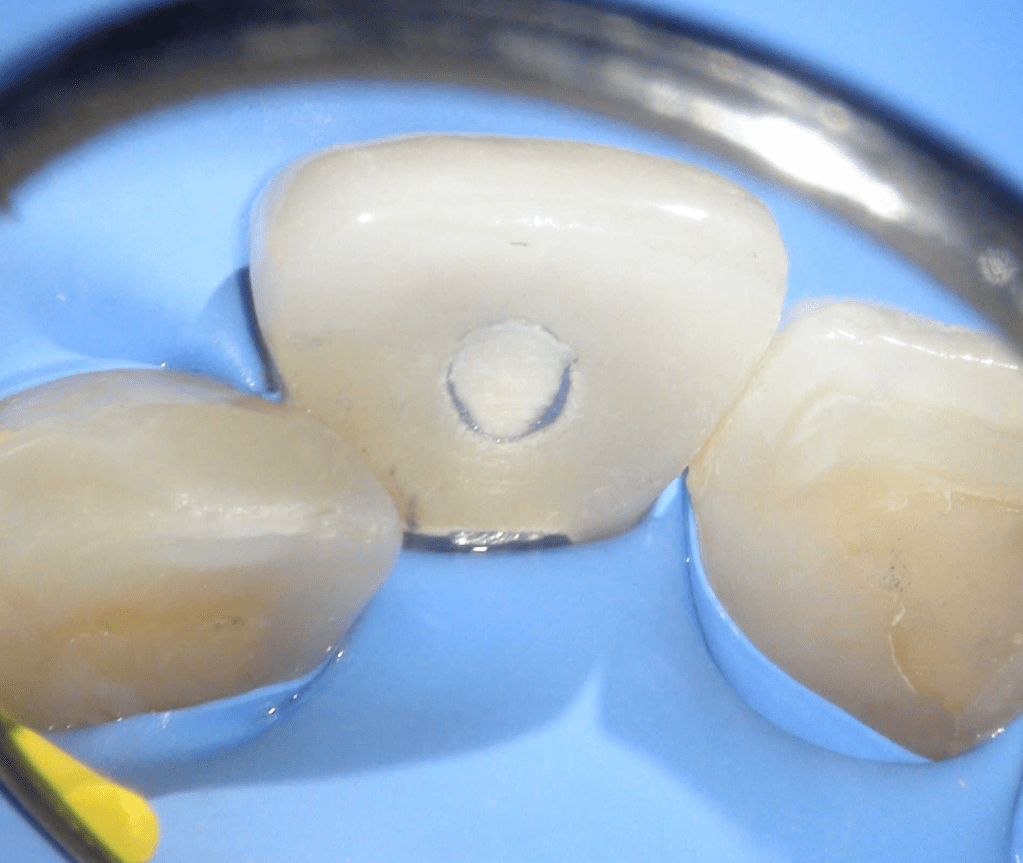

Acceso ultraconservador a través de incrustación reciente